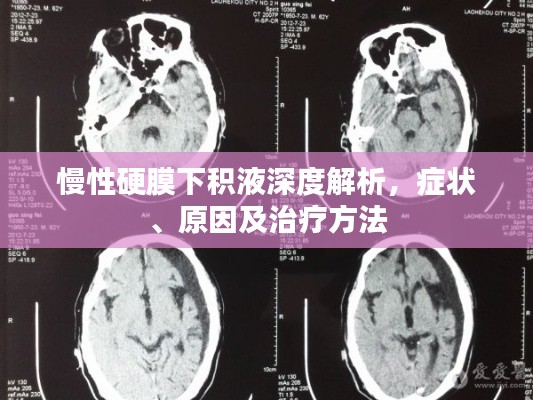

诊断与治疗

对于慢性硬膜下积液的诊断,通常需要进行头颅CT或MRI等影像学检查,治疗方法主要包括药物治疗和手术治疗,药物治疗主要是对症治疗,如使用脱水药物降低颅内压等,对于严重的慢性硬膜下积液,可能需要手术治疗以消除积液并恢复颅内压力平衡。